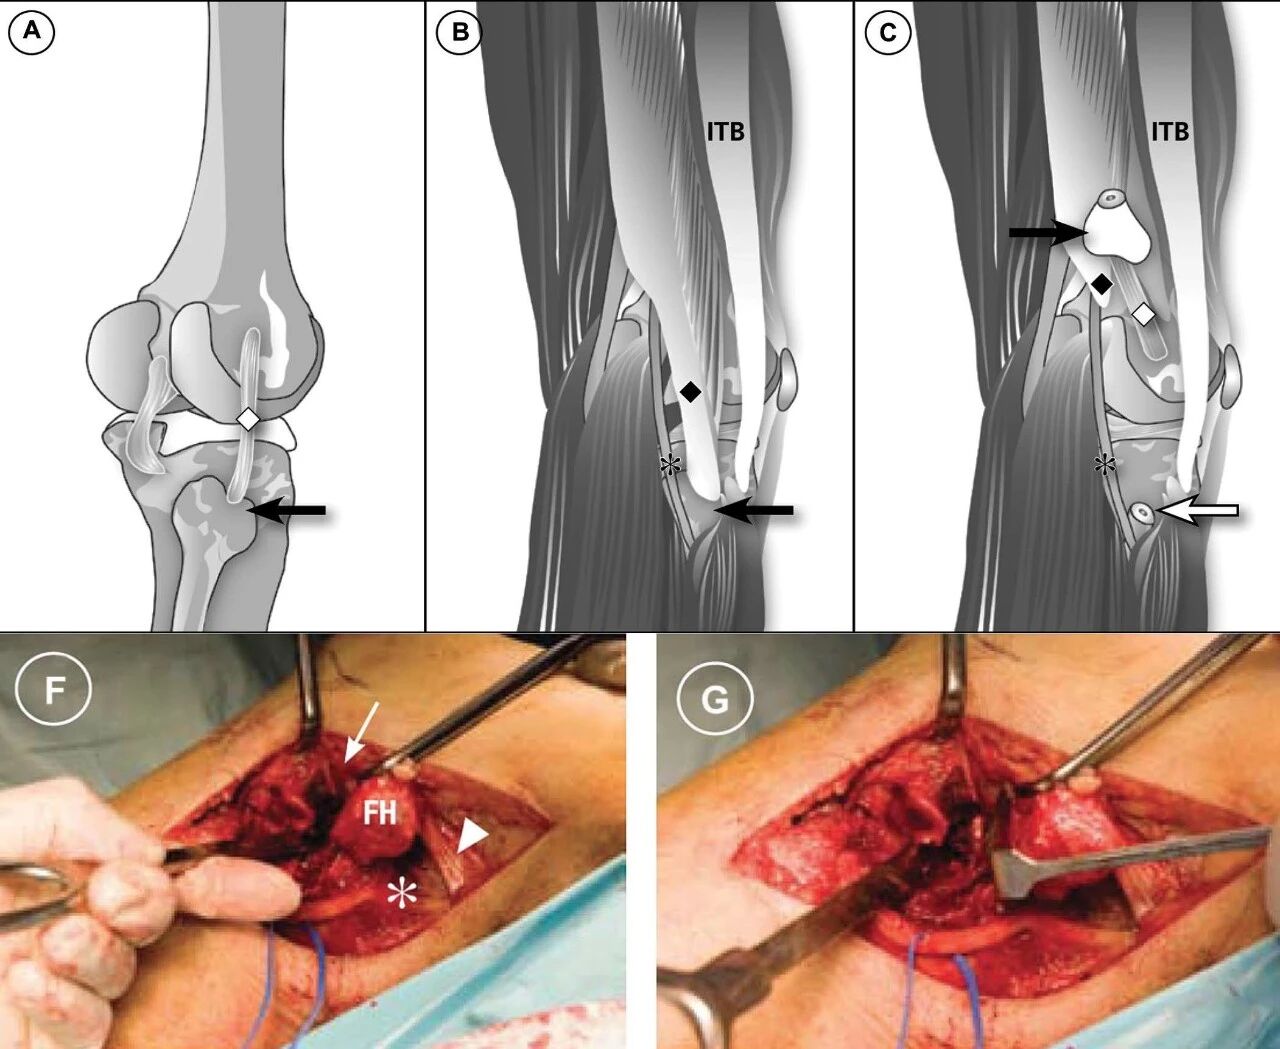

▲ 图3(来源:Solomon #2010年文章,他提出在仰卧位采用腓骨颈截骨直接显露后外侧,*腓总神经,FH腓骨头)

腓骨颈截骨的优势是在一定程度上扩大了后外或外侧入路的显露范围,但与Carlson入路一样,该入路也需注意避免损伤腓总神经,其远端显露也同样受限。此外,截骨还可能引起术后骨不连和附着于腓骨头的韧带损伤问题。

相比腓骨颈截骨,俞光荣所提出的腓骨头纵行截骨入路一定程度上改善了腓骨颈横行截骨所带来的问题。